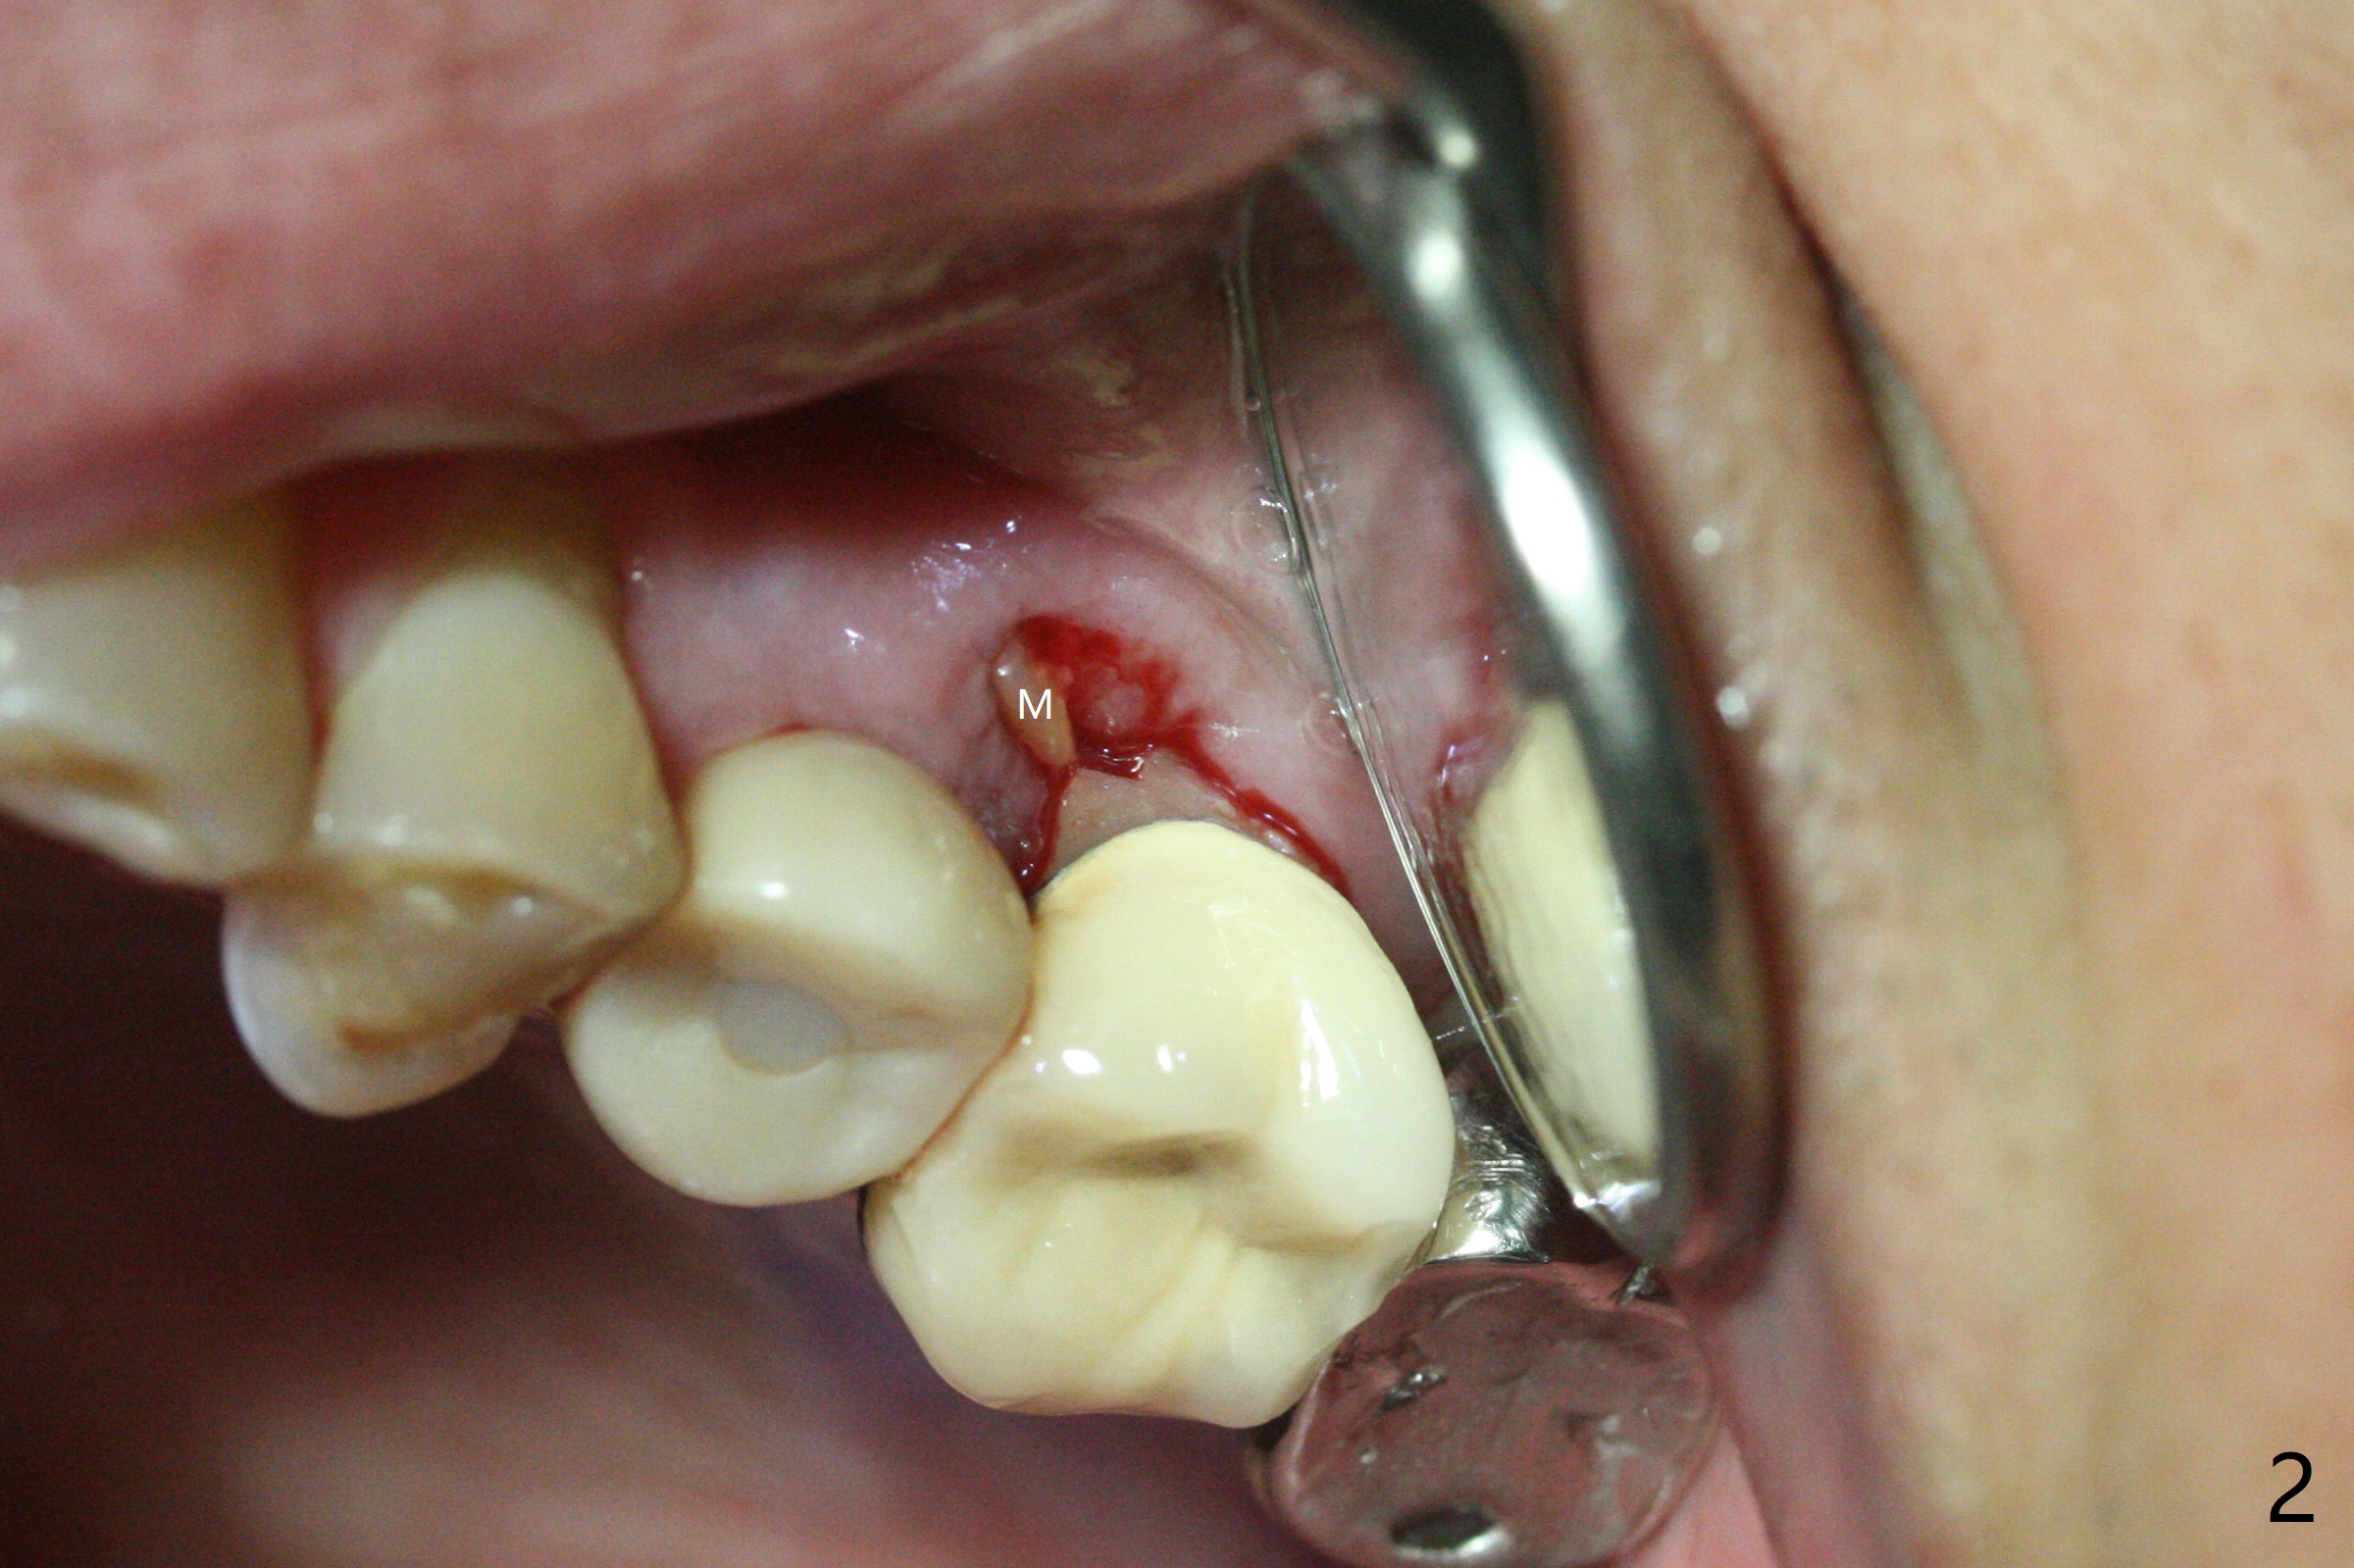

The vertical mesiobuccal root fracture of #14 of a 59-year-old man has become worse in the last 10 months. The mesial portion appears to be separate and have migrated mesiobuccal from its original place (Fig.1,2). CT taken 10 months earlier shows that the septal bone seems to be thin (Fig.3). Use IS drills (pointed to 3 mm in diameter) with 2 or 3 mm stoppers to start osteotomy and Magic Sinus Lifter. Place a 4.5x9 mm FC. If the latter fails, use sticky bone for sinus lift and socket preservation, followed PRF membranes (3-4), Cytoplast (small piece, smaller than the wound) and setting acrylic to close the sockets, including buccal defect. Take new CT (5x5) for update.